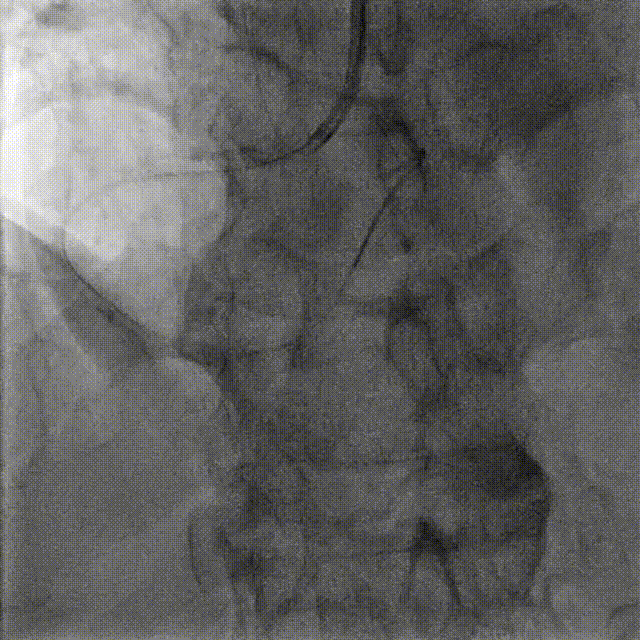

CAG-LCA-钙化、 分叉 、弥漫病变 TR, 5F TIG

CAG-RCA -钙化,开口,弥漫病变 TR, 5F TIG

病变特点:

RCA:钙化,开口,弥漫病变

LAD:钙化,分叉,弥漫病变

LCX:细小,可不处理